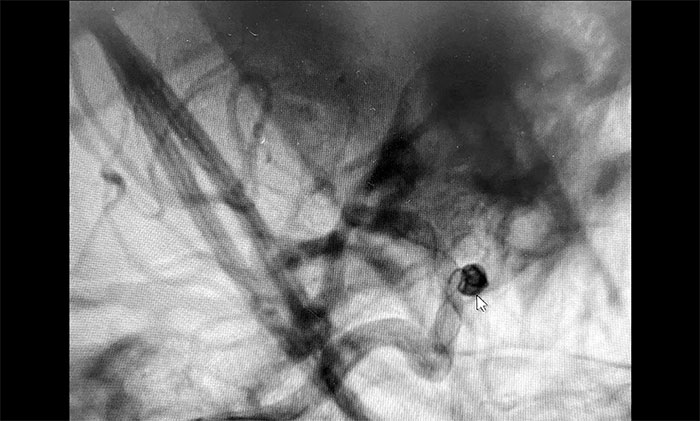

▲動脈瘤栓塞

術(shù)中,在微導(dǎo)絲的引導(dǎo)下將微導(dǎo)管頭端小心送入動脈瘤腔內(nèi),之后順著這個通路往動脈瘤內(nèi)填塞彈簧圈,造影顯示動脈瘤瘤內(nèi)造影劑明顯滯留,眼動脈(載瘤動脈)血流通暢。遂解脫彈簧圈并釋放支架,再次造影,支架覆蓋動脈瘤,貼壁良好。整臺手術(shù)歷時90分鐘順利完成,患者術(shù)后恢復(fù)情況良好。